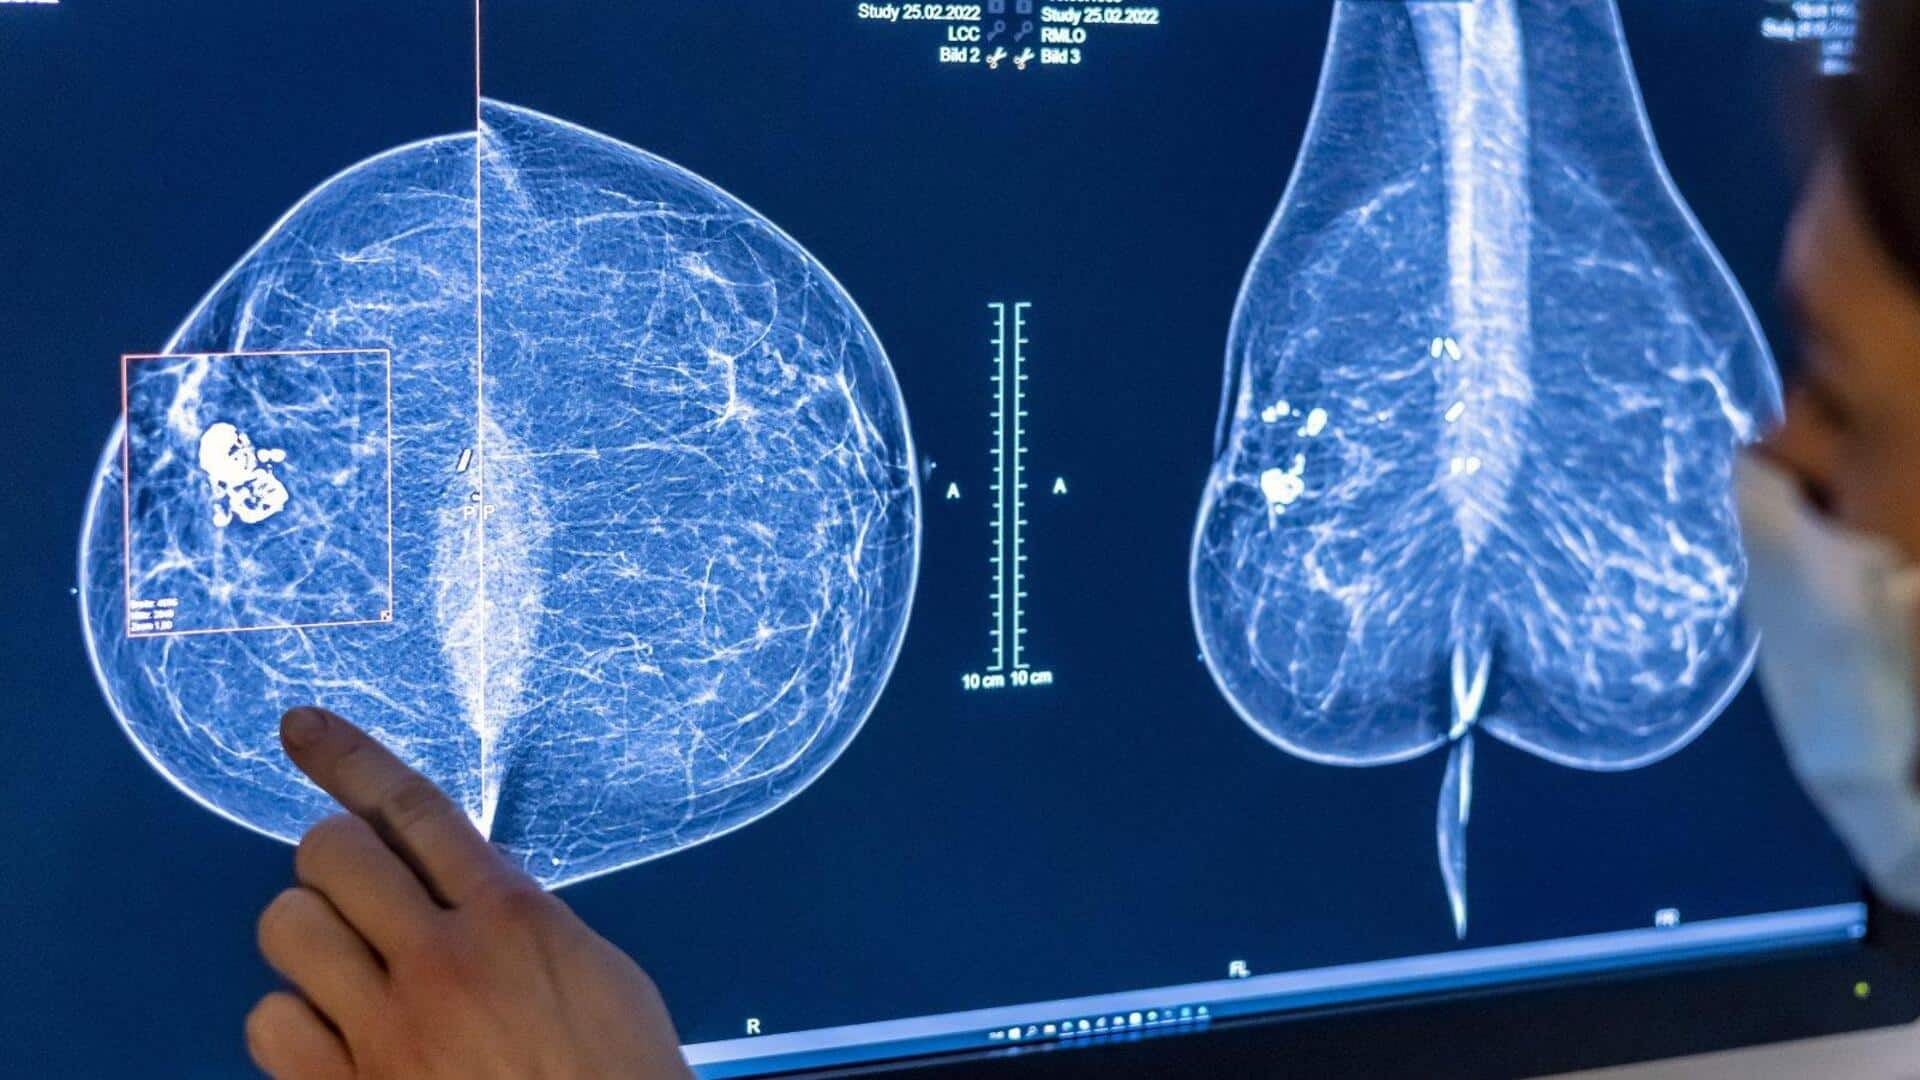

రొమ్ము క్యాన్సర్ స్క్రీనింగ్‌లో కృత్రిమ మేధస్సు (AI) వినియోగం వల్ల తరువాతి సంవత్సరాల్లో క్యాన్సర్ నిర్ధారణ రేటు 12 శాతం తగ్గిందని,అలాగే ప్రారంభ దశలోనే క్యాన్సర్ గుర్తించే అవకాశం పెరిగిందని తాజా అధ్యయనం వెల్లడించింది. ఇదే తొలిసారి ఈ స్థాయిలో నిర్వహించిన ట్రయల్ కావడం విశేషం. ఈ అధ్యయనం ఇప్పటివరకు రొమ్ము క్యాన్సర్ స్క్రీనింగ్‌లో AI వినియోగంపై చేసిన అతిపెద్ద పరిశోధనగా శాస్త్రవేత్తలు చెబుతున్నారు. స్వీడన్‌లోని 1లక్ష మంది మహిళలను ఈ అధ్యయనంలో భాగం చేశారు. 2021 ఏప్రిల్ నుంచి 2022 డిసెంబర్ వరకు మామోగ్రఫీ పరీక్షలు చేయించుకున్న మహిళలను యాదృచ్ఛికంగా రెండు గ్రూపులుగా విభజించారు. ఒక గ్రూప్‌కు AI సహాయంతో స్క్రీనింగ్ చేయగా,మరో గ్రూప్‌లో ఇద్దరు రేడియాలజిస్టులు సాధారణంగా పరీక్షలు చేశారు.

AI సిస్టమ్ మామోగ్రామ్ చిత్రాలను విశ్లేషించి,తక్కువ ప్రమాదం ఉన్న కేసులను ఒక్క రేడియాలజిస్ట్‌కు,ఎక్కువ ప్రమాదం ఉన్న కేసులను ఇద్దరు రేడియాలజిస్టులకు పంపింది. అలాగే అనుమానాస్పద అంశాలను హైలైట్ చేసి డాక్టర్లకు సహాయం చేసింది. ది లాన్సెట్ జర్నల్‌లో ప్రచురితమైన ఈ అధ్యయనం ప్రకారం,AI మద్దతుతో చేసిన మామోగ్రఫీ స్క్రీనింగ్‌లో తరువాతి సంవత్సరాల్లో క్యాన్సర్ నిర్ధారణ రేటు 12 శాతం తగ్గింది. AI గ్రూప్‌లో ప్రతి వెయ్యి మంది మహిళల్లో 1.55 మందికి క్యాన్సర్ గుర్తించగా,కంట్రోల్ గ్రూప్‌లో ఇది 1.76గా నమోదైంది. AI సహాయంతో చేసిన స్క్రీనింగ్‌లో 81 శాతం క్యాన్సర్ కేసులు పరీక్షల సమయంలోనే గుర్తించబడగా, సాధారణ విధానంలో ఇది 74 శాతమే.